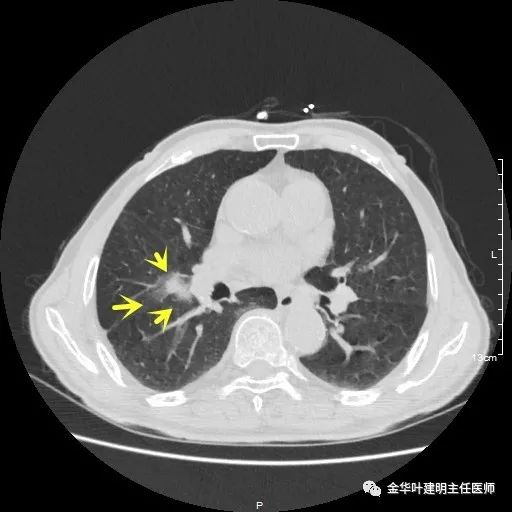

以上示右肺中叶病灶3。是混合磨玻璃结节,位置差,邻近肺门部,无法局部楔形切除,抗炎治疗后靶扫描显示了更清楚的细节,是典型的肺癌影像特征(此处未另提供)。从单病灶来看,需要行右肺中叶切除并清扫淋巴结才能得以治疗。

以上示右中叶病灶4。也是囊腔型病灶,病灶大,囊壁是磨玻璃密度,亦是较为典型的囊腔型肺癌影像。单病灶看,需中叶切除来治疗,因病灶3的存在,中叶切除可同时解决病灶3与病灶4。